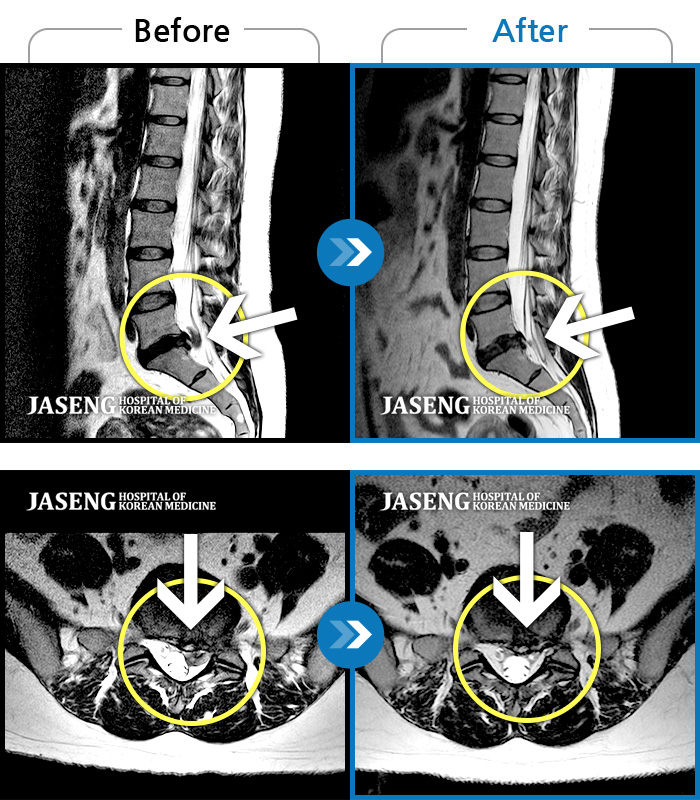

ȯںп Ǹ ǿ ԿǾ, ο ġ ۿ Ƿ ġḦ Ͻñ ٶϴ.